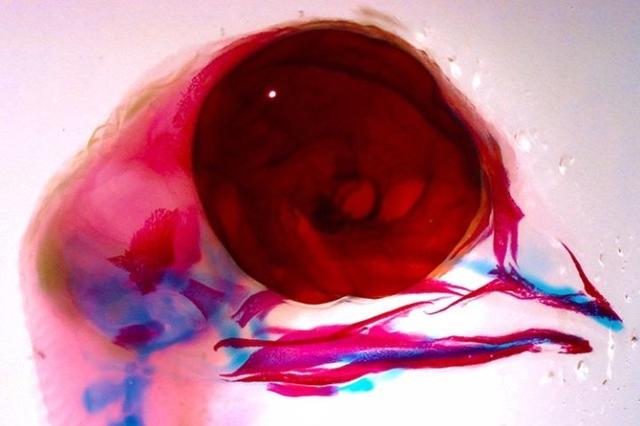

最近一期Science Signaling的封面照片上展示的一张鸡胚胎的颅面透视照片。科学家用蓝色和红色标记了不同组织。研究高温对鸡胎可能造成的损伤。图片来源:Science Signaling | Liu, et al.

暴露在高温环境中的鸡胚出现了先天性心肌缺损的情况。图片来源:Duke Health

高温导致鸡胎出现了严重的颅面部畸形。与左边正常的胚胎相比,高温严重缩短了鸡胚胎的上喙(右)。图片来源:参考文献[4]

在进一步的研究中,科学家发现,神经嵴上有两个与温度相关的离子通道:TRPV1和TRPV4。它们在神经嵴向心脏和颌面部分化时起着非常重要的作用[4]。研究者用发育模式和人类相似的鸡胚做实验,结果发现:与在适宜环境中正常发育的鸡胚相比,在40~41℃的环境中暴露过一小时后再孵化的鸡胚,喙发育缺陷和心血管缺陷都有明显的增加。同时,研究者们还设计了诸如高温下抑制TRPV1和TRPV4、常温下激活TRPV1和TRPV4的动物实验作为对照,证实了这两个离子通道在高温致畸机制中的重要地位。